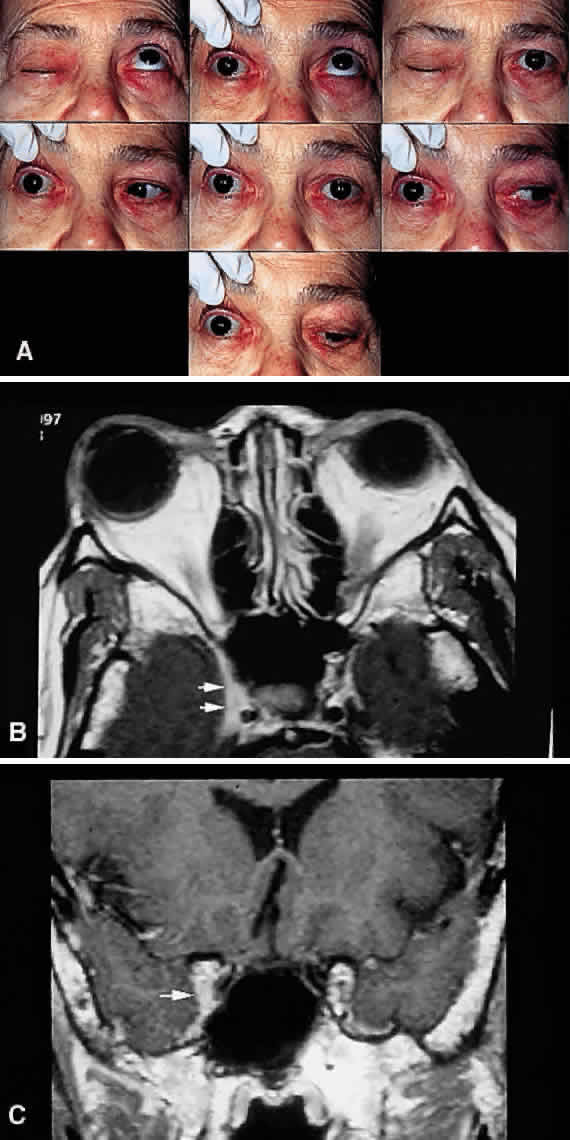

are seldom as distinct as described in Table 8.  Fig. 15. Parasellar syndrome. A. Composite photograph of an elderly patient with periorbital pain in the

distribution of the right supraorbital nerve along with complete ptosis

and absent levator function (upper left and upper right). When the

eyelid was lifted, she complained of diplopia (center). Note the complete

external ophthalmoplegia (remaining panels). MRI revealed a mass

eroding the anterior clinoid process and extending into the CS and surrounding

brain parenchyma. Given the bony erosion, a diagnosis of Tolosa-Hunt

would be inappropriate in this case. A transorbital craniotomy

for biopsy revealed metastatic adenocarcinoma. A systemic workup failed

to reveal a primary site of involvement. The patient' orbital signs

responded to radiation therapy. B and C. Axial and coronal MRI of a different patient who presented in an identical

fashion. Note the enlargement of the right CS (arrows). Systemic workup was negative, and the patient responded rapidly to intravenous

corticosteroids. The lesion disappeared on subsequent scans

with no evidence of recurrence after 2 years. A diagnosis of “presumed

Tolosa-Hunt syndrome”is acceptable in this case. Fig. 15. Parasellar syndrome. A. Composite photograph of an elderly patient with periorbital pain in the

distribution of the right supraorbital nerve along with complete ptosis

and absent levator function (upper left and upper right). When the

eyelid was lifted, she complained of diplopia (center). Note the complete

external ophthalmoplegia (remaining panels). MRI revealed a mass

eroding the anterior clinoid process and extending into the CS and surrounding

brain parenchyma. Given the bony erosion, a diagnosis of Tolosa-Hunt

would be inappropriate in this case. A transorbital craniotomy

for biopsy revealed metastatic adenocarcinoma. A systemic workup failed

to reveal a primary site of involvement. The patient' orbital signs

responded to radiation therapy. B and C. Axial and coronal MRI of a different patient who presented in an identical

fashion. Note the enlargement of the right CS (arrows). Systemic workup was negative, and the patient responded rapidly to intravenous

corticosteroids. The lesion disappeared on subsequent scans

with no evidence of recurrence after 2 years. A diagnosis of “presumed

Tolosa-Hunt syndrome”is acceptable in this case.